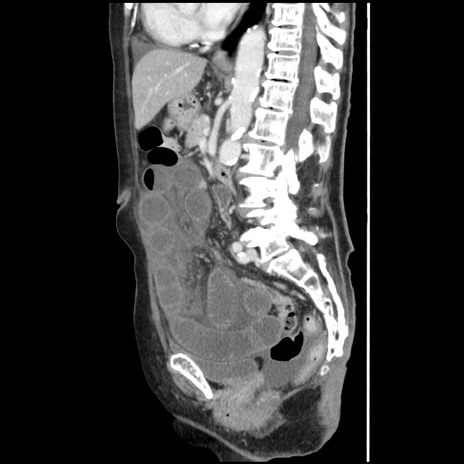

症例1(矢状断像)

【症例】80歳代女性

【主訴】腹痛

【現病歴】8時間前から腹痛あり来院。

【既往歴】糖尿病、脂質異常症、子宮体癌にて子宮全摘術

【身体所見】意識清明・会話良好だが腹痛で苦悶様、全腹部にわたって反跳痛と圧痛あり

【データ】WBC 13600、CRP 0.14、LDH 224、CK 90